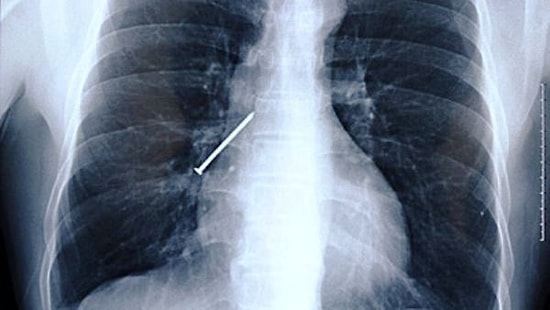

Удивительное рядом: 14 самых неожиданных вещей, найденных у пациентов при рентгене

Что бы мы делали без хирургов! Именно они спасают нас в глупейших ситуациях, когда приходится вытаскивать всякие штуки-дрюки. 'Такое происходит только с настоящими растяпами', - скажете вы. А вот и нет. Один товарищ, например, случайно проглотил маникюрные ножницы, которые использовал вместо зубочистки.У другого товарища обнаружили посторонний предмет, забытый внутри после операции 18 лед назад. В общем, ситуации самые разные. А уж предметы и подавно: зажигалки, фонарики, бутылки, гвозди. И даже живые лягушки 🙊